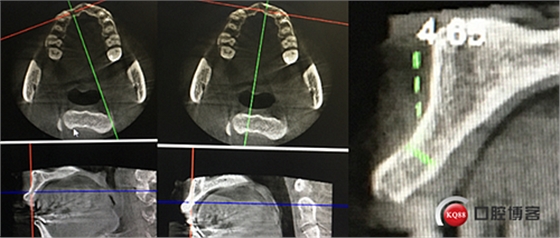

“以修復為導向”,在前牙種植體中心點就是未來牙冠舌側(cè)窩位置。那這個病例植體的方向和位置就只能是下圖右側(cè)這樣了。很明顯植體根尖部分要穿出唇側(cè)倒凹的。怎么辦?翻大瓣植骨蓋膜減張縫合?不!可以不翻瓣,大家仔細看看下圖右圖我畫的那條細細的弧線,是不是跟原來唇側(cè)凹陷的骨面成為左右對稱的兩條弧,也就是說骨膜從原來唇側(cè)凹陷骨面上剝離然后放到左側(cè)我畫的那條弧線那里根本不需要減張,這兩條弧線之間也就是唇側(cè)凹陷處放上骨粉,骨膜不會增加張力。不知道大家看明白了沒有。